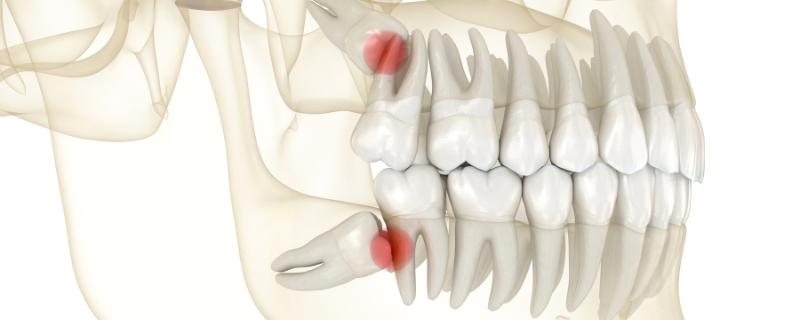

口腔外科出身の院長が担当

親知らずの即日抜歯に対応

親知らずの痛みは急にやってきます。当院では「親知らず外来」を設け、口腔外科出身の院長が迅速かつ安全に抜歯を行います。CTによる正確な診断に基づき、初診当日の抜歯にも対応可能です。抜歯に強い恐怖心がある方には、眠っている間に治療が終わる静脈内鎮静法も行えますので、我慢せずご相談ください。